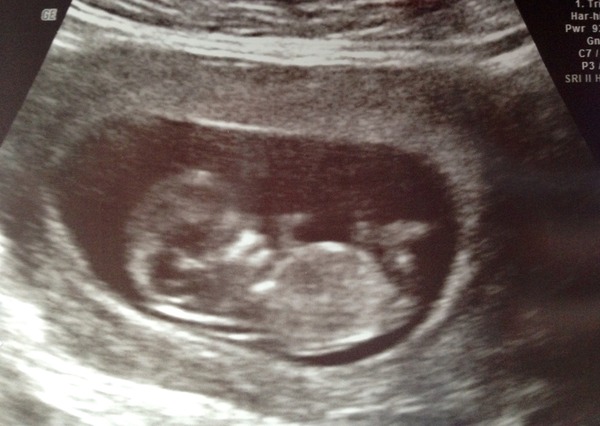

I've been busy or completely wiped out for past ten days with cold, birthday and visitors. All over now but we are travelling to in-laws tmrw, (with private scan en route, eek! ) and have nothing packed! DH doing my head in. Think he is getting nervous about the scan too, and slightly freaking out about impending fatherhood. Yesterday he was acting very weird & pensive in the morning - while I was dashing around wrapping presents, posting Christmas cards to his family and icing the cake, making lists, etc. It didn't help that he was hung over after drinking with visiting buddy. Then last night as he wanted to stay out drinking with the same friend despite the fact that we have loads to do today and we had all four of us agreed it would be an early night, as the friends are leaving tmrw. I was so upset! Told him off in front of them, although because they don't know I'm pregnant I just looked like a b*tch. Felt so tired and overwhelmed and unsupported. He came home after that, but fell asleep on the couch snoring so I just left him and went to bed.

Sorry for the big vent! I am so sick of keeping it a secret and having to invent excuses for not drinking and for being so tired, and for letting a cold get me down this much. And I'm worried about the scan too! But I really need everything to be organised today so I can get some sleep before we leave at 6am this morning...And we are going to see Star Wars at 6 with DH and his friends.

Birthday a bit of a weird one this year - went for dinner with DH. It was lovely, but I usually go to the pub for food & drinks, and invite everyone I know! If people haven't guessed already, they will have now I reckon. Thankfully we can tell everyone after the hols, if all goes well at the scan. Hope it does!